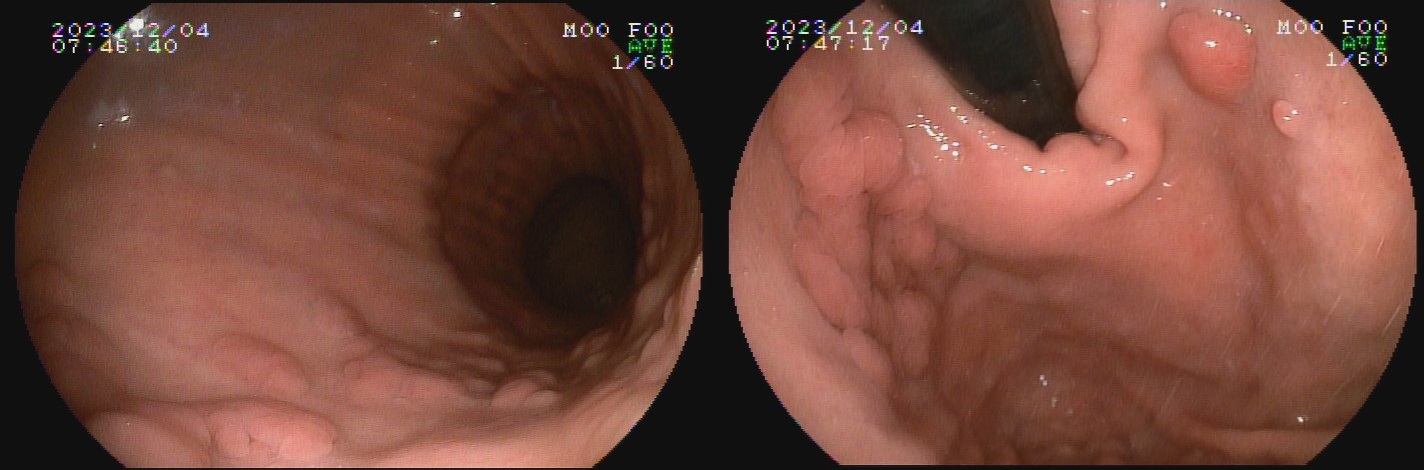

Já a gastrite atrófica autoimune ocorre por destruição glandular por autoanticorpos anticélulas parietais, e é mais comum em mulheres, porém dados relativos à idade e etnia mais frequente são controversos. A inflamação crônica resulta em redução do relevo e palidez da mucosa de fundo e corpo, assim como desaparecimento do pregueado mucoso observado à insuflação durante o exame endoscópico, com aspecto mais homogêneo que aquele encontrado na gastrite atrófica infecciosa. Podem ser formadas ilhas de mucosa normal residual, caracterizadas endoscopicamente como pseudopólipos. A mucosa do antro mantém-se preservada por não apresentar células parietais, delimitando uma área de transição clara entre a mucosa atrófica do corpo e mucosa normal do antro.